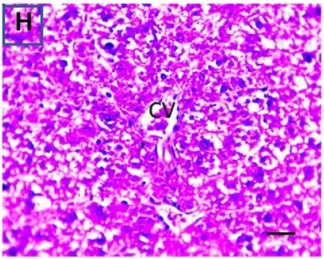

Put the liver tissue section under a microscope, and you can see that cisplatin can cause liver congestion (the blood that should return to the heart is blocked and stagnates in the hepatic veins), cell degeneration (vacuoles appear, which is the earliest change in cellular injury), apoptosis and necrosis, but these conditions can also be alleviated by using Ganoderma lucidum.

Figure 2 Effects of cisplatin and Ganoderma lucidum on hepatocytes